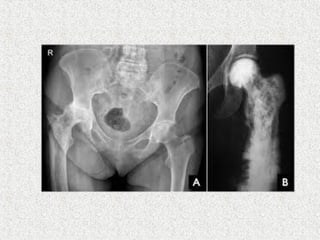

 NOF

 Prosthetic replacement

 Severe disabling arthritis

 THR

 Significant varus deformity

 Bowing

 Acetabular protrusion

 Increased blood loss

 Distorted medullary cavity

 Sclerosis

 Heterotrophic ossification

 Fracture  NOF Prosthetic replacement  Subtrochateric femur  Intramedullary system  Corrective osteotomy  Most pathological long bone #  Intramedullary system  Even after union protective bracing for 3-6 months  Because remodelling is slow

 Severe disablingarthritis  THR  Significant varus deformity  Bowing  Acetabular protrusion  Increased blood loss  Distorted medullary cavity  Sclerosis  Heterotrophic ossification